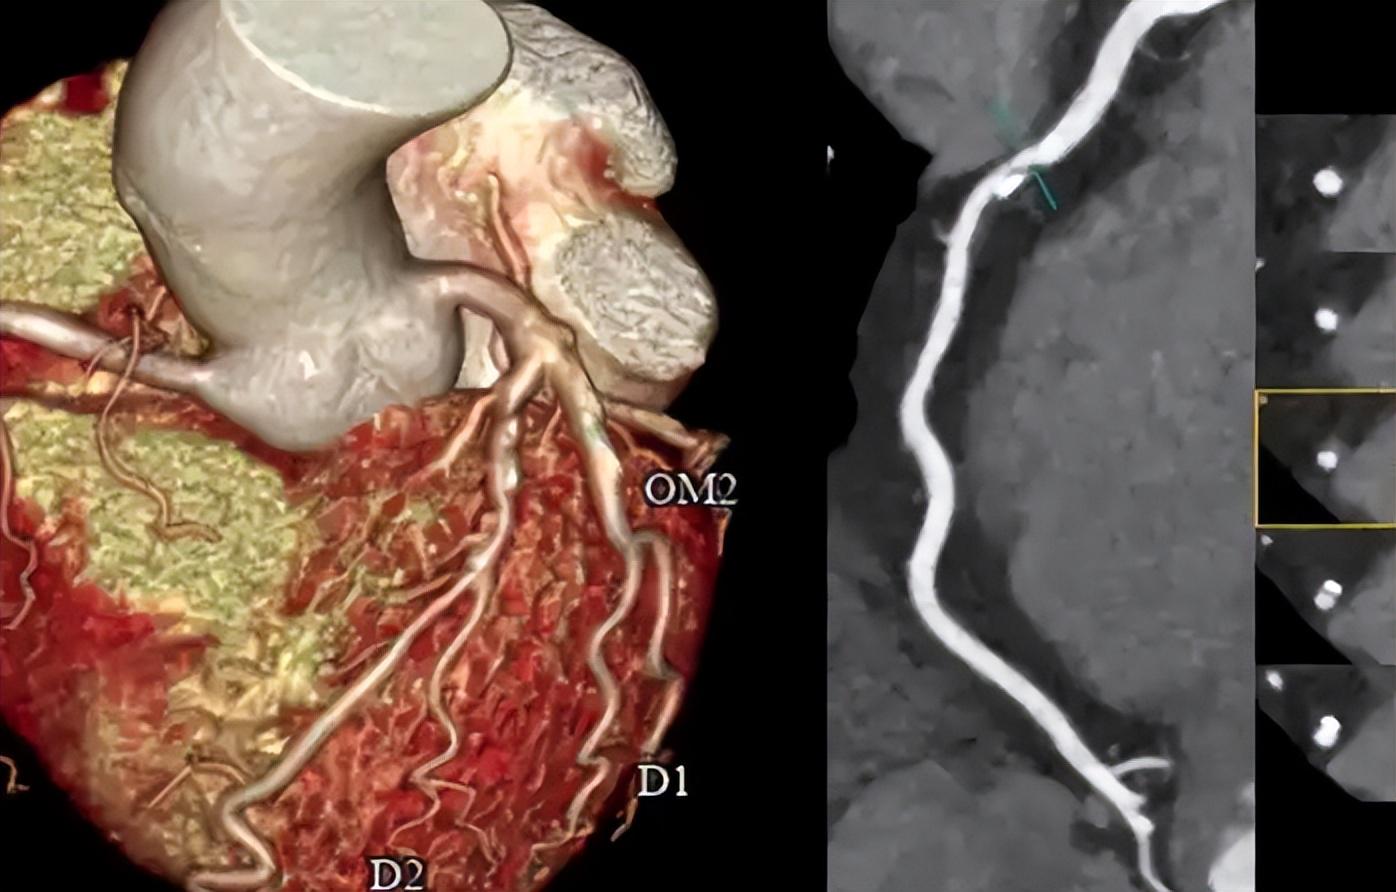

还有一种“静悄悄”的心梗,叫做微血管心绞痛。这类人平时体检指标正常,但就是胸口总觉得堵得慌,一检查心电图也没啥问题,但做冠脉CT或者心脏核磁,才发现问题藏在微血管里。